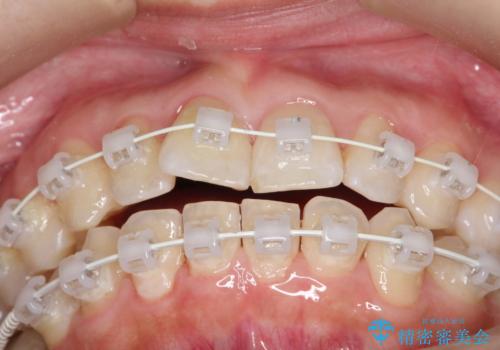

- 矯正装置

- 審美ワイヤー装置

- 患者様は、右下第二小臼歯が舌側に転移していることが主訴でした。診断の結果、抜歯を伴う矯正治療も検討しましたが、奥歯の遠心移動とIPR(インタープロキシマルリダクション)を行うことで、非抜歯で矯正を進めることが可能であると判断しました。治療計画では、審美ワイヤーを用いた2年間の治療で、歯列を整えつつ、臼歯関係や正中のバランスを維持しながら進めました。

非抜歯矯正では、歯の動きを慎重に調整することが求められます。本症例では、奥歯を遠心に移動させることで、舌側に転移した右下第二小臼歯の位置を改善しました。また、IPRを行うことで歯間スペースを確保し、無理なく歯列の調整を行いました。非抜歯での治療は、特に臼歯関係や正中を保ちながら治療できるというメリットがあり、最終的にはバランスの取れた歯並びを実現できました。審美ワイヤーを使用したことで、治療中も目立ちにくく、患者様の見た目にも配慮した治療を行いました。